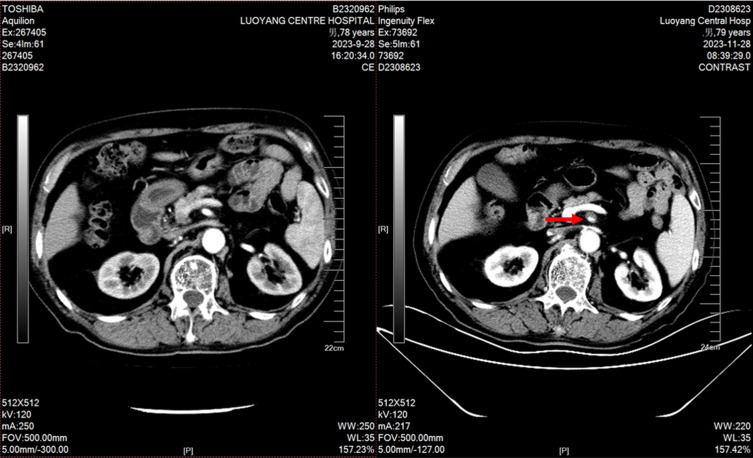

Background: Apatinib mesylate, a VEGFR2 tyrosine kinase inhibitor, is approved for advanced liver, esophageal, gastric and other malignant tumors, but its adverse effects require attention. We report a 79-year-old male with prostatic adenocarcinoma who developed superior mesenteric artery dissecting aneurysm after combined apatinib and chemotherapy. Apatinib, an anti-angiogenic agent, synergizes with chemotherapy. After informed consent, the combination regimen was initiated. Two cycles later, the patient had tolerable intermittent abdominal pain, and CT confirmed the aneurysm. Due to progressive tumor and poor physical status, no further treatment was given as the aneurysm did not affect the disease course. This case report aims to provide insights into the safe application of apatinib in clinical practice.

Case report: In this case report, a 79-year-old male with a height of 172 cms and a weight of 67 kgs who had been diagnosed with prostate adenocarcinoma for over three years. MRI scan indicated that bone metastases increased and enlarged compared with prior test. No significant abnormalities were observed in both physical and blood examinations. The pelvic MRI scan showed a prostatectomy changes, multiple abnormal signals in the bilateral ilium, acetabulum, femur, ischiatic bone, pubis, sacral vertebrae, and part of the lumbar vertebrae.